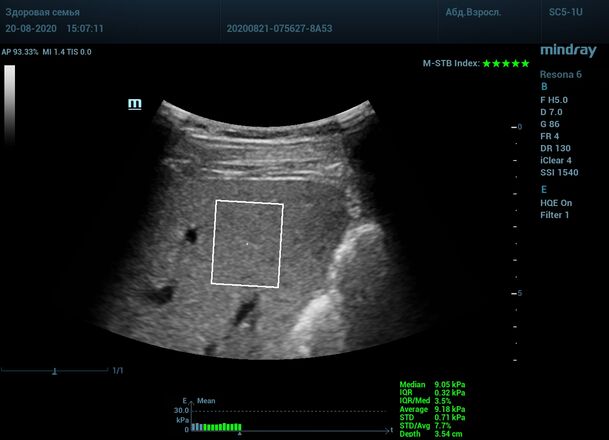

Как работает эластография сдвиговой волны? Датчик посылает плотный пучок ультразвуковых волн в ткани, ткани сжимаются, а затем возвращаются в исходное состояние за счет своей эластичности. Расправление ткани создают поперечные ультразвуковые волны, которые регистрируются трансдьюссером. Прибор во время исследования непрерывно отображает график значений плотности печени (kPa) в исследуемой зоне, достоверным считается график в виде прямой линии. Такая линия формируется путем получения близких по значению показателей. Количественным показателем является отношение межквартального интервала к медиане (IQR/Med). Допустимым считается результат с IQR/Med менее 30%. Чем данный показатель меньше, тем более точным является исследование. Для достоверного исследования в идеале нужно 10 значений.

Для таких сложных случаев в приборах Mindray Resona предусмотрен режим HQ Elasto. В отличии от стандартной работы эластографии HQ Elasto позволяет собрать отдельное короткое измерение в сборный график. Достаточно задержки дыхания всего в пару секунд, показатель будет записан и добавлен в график измерений. Таким образом, короткими «залпами» ультразвуковых волн по печени доктор без проблем соберет все необходимые 10 значений и проведет автоматический анализ с расчетом медианы и IQR/Med.

Приводим видео пример: использованы 3 точки доступа печени, каждое значение графика получено прицельным выстрелом HQ Elasto и собрано в единый тренд. В результате анализа 10 значений получен удивительно точный результат - статистический разброс  3.5 % IQR/Med.